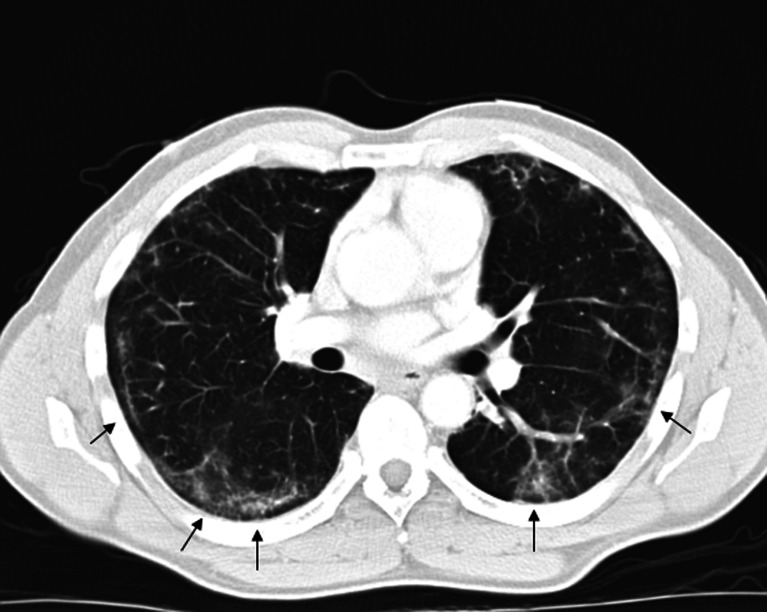

Chest X-ray demonstrated bibasilar patchy infiltrates. Chest computed tomography (CT) revealed bilateral peripheral and lower lobe interstitial infiltrates with air bronchograms (see Fig. 1).

Figure 1.

Chest computed tomography (CT) with peripheral interstitial ground-glass infiltrates (arrows).